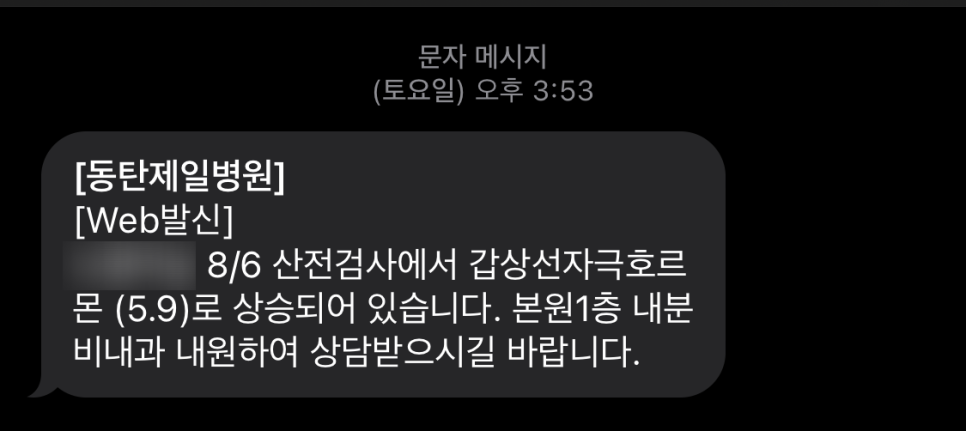

6주차에 간 산전검사 결과를 듣기위해 8주차에 재방문! 원래 정확히 2주후인 8주4일로 예약을 잡았는데…무서운 메일을 받았다.

뭐..?

갑상선 자극 호르몬 수치가 높나요?내 인생에서 건강검진을 받고 이렇게 비정상적인 수치를 받은 적은 거의 없는데…(건강검진으로 줄일 수 있다고는 하지만)

이 수치가 얼마나 높은지 감도 안잡히고…불안하기 짝이 없는 무한 검색만 했어.

이 메일을 받고 너무 무서웠는데, 광복절 연휴가 있어서 바로 병원에 갈 수가 없었어(´;ω;`)

내분비내과 검진 산전검사 후 갑상선 수치메시지를 받고 방문했다고 접수를 하고 내분과 내과 1과 선생님에게 진료를 받았다.

내가 생각했던 대로 갑상선 기능 저하증이었어

임신초기의 정상범위보다 2배이상 나왔네…ㅠㅠ이건 뭐야ㅠㅠ